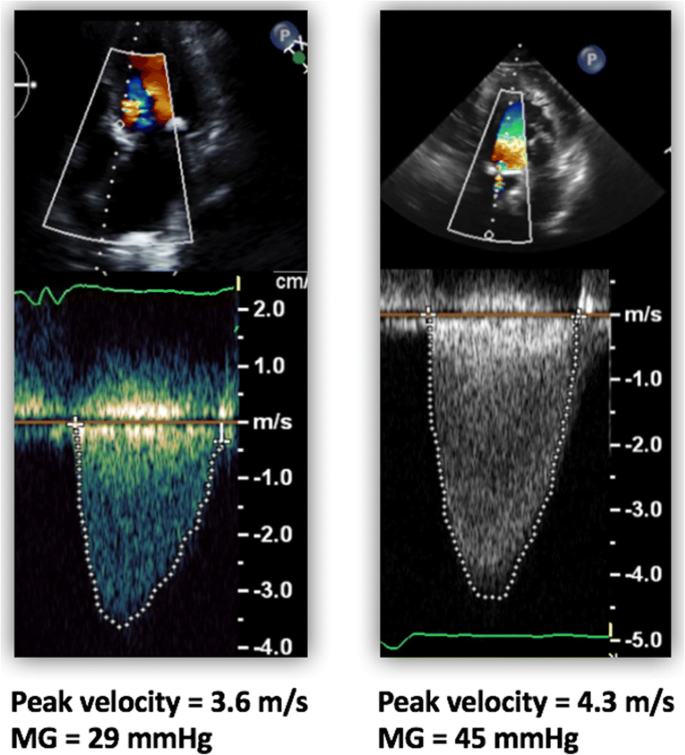

Find More Information on Cardiovascular Disease View a Treatment Option. The transvalvular gradient is highly dependent on the flow of blood through the valve. Aortic stenosis AS is 1 of the most common valve disorders encountered in.

Doppler Echocardiographic Quantitation Of Aortic Valve Stenosis A Science In Constant Evolution Journal Of The American Society Of Echocardiography

Aortic Stenosis Prognosis With Doppler Echocardiography As